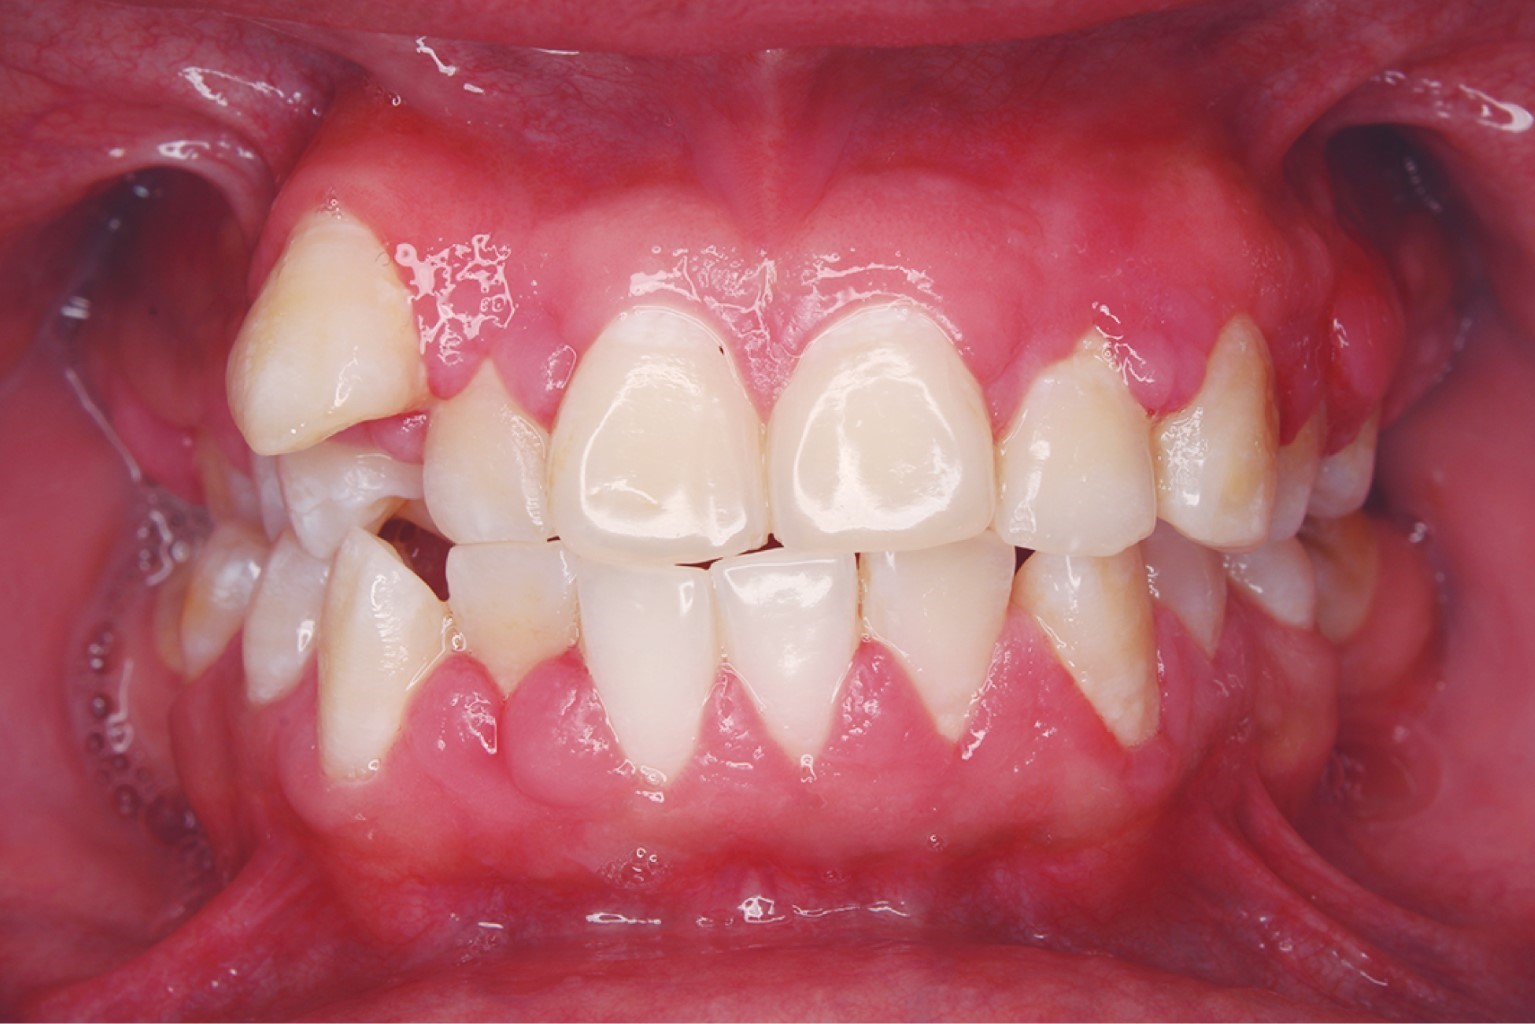

Al realizar el examen clínico se observó presencia generalizada de placa dentobacteriana y malposición dental, aumento de volumen en la encía en las caras vestibulares y palatinas del sextante #2, y en la cara vestibular del sextante #5 de color rosa pálido con márgenes eritematosos y nodulares cubriendo un tercio de la corona clínica, al momento de sondear hubo presencia de sangrado (Figura 1).

Figura 1